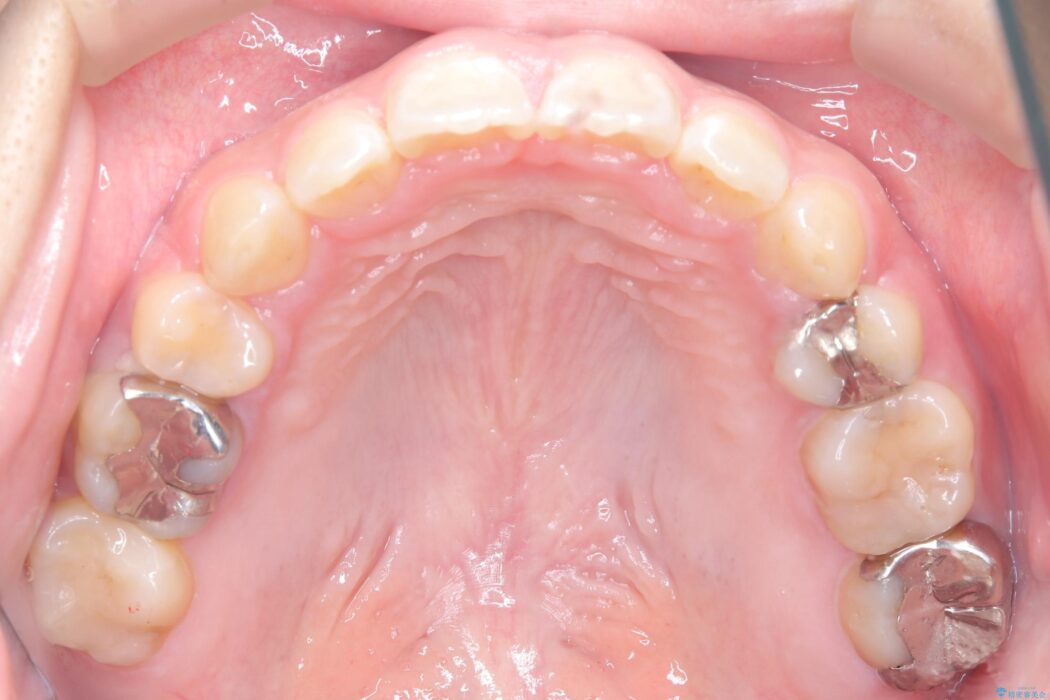

精密検査の結果、前歯を大きく後退させるスペースが必要と診断しました。

「前歯を下げたい」という患者様の強いご希望に応えるため、上下左右の第一小臼歯を抜歯。そのスペースを利用し前歯を奥へ移動させる治療計画を立案しました。

装置は人目を気にせず治療できるよう、上顎に裏側矯正、下顎に表側矯正を組み合わせたハーフリンガル矯正を提案しました。

今回の矯正治療では、前歯を大きく後退させるスペースを確保するため、計画通り上下左右の第一小臼歯を抜歯しました。

装置には、上顎には目立たない裏側矯正(舌側矯正)を、下顎には透明な審美ブラケットを使用するハーフリンガル矯正を採用しました。抜歯によってできたスペースを最大限に活用し、前歯を効率よく後方へ移動。治療の結果、口元の突出感が大幅に解消され、Eライン(横顔の美しさの基準)も改善しました。人目を気にすることなく治療を完遂し、自信の持てる美しい横顔を獲得していただけました。